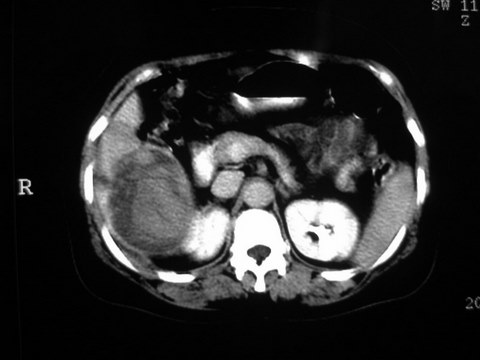

患者 女 51岁 两天前感觉上腹疼,无明显诱因,b超示肝右叶囊实性占位,边缘清楚,其内回声不均匀,ct增强如图,大家看看是什么 ,病人一年前及两月前b超检查只是提示胆囊炎

外院术后,证实肝癌合并出血

特点:1,病灶发展迅速,(2月前正常)[br] 2,囊实性,且并边界清晰光滑,呈右后叶赘生性。囊性区无强化,实性部分较多轻度强化,边界欠清。考虑囊腺癌或囊腺瘤。

出病理 中分化肝细胞癌合并出血